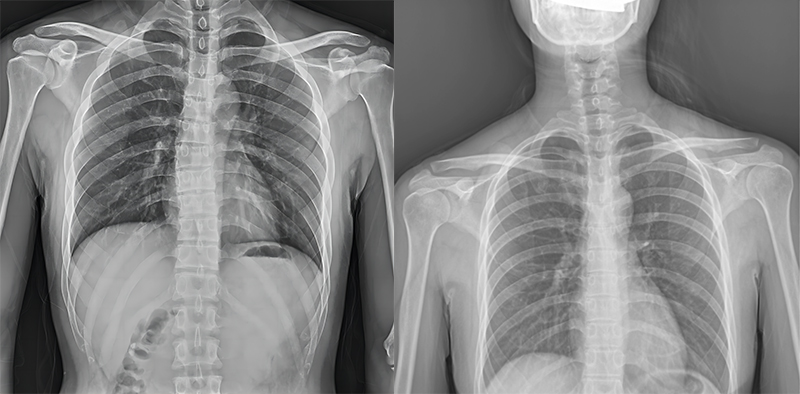

百微米DR與普通像素尺寸DR的影像對(duì)比

以胸部攝影為例,通過對(duì)比百微米大平板與普通像素尺寸平板的影像,可以看到百微米影像對(duì)比度適中,圖像清晰度更高,成像細(xì)節(jié)更加豐富。在胸部影像顯示中肺門影結(jié)構(gòu)、肺紋理等細(xì)節(jié)展示更清楚,兩側(cè)膈肌邊緣、心臟、縱隔邊緣清晰銳利顯示,在影像中都可以清晰地顯示胸部細(xì)微結(jié)構(gòu),滿足臨床診斷要求。